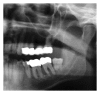

Infections are increasingly considered as potential trigger for carcinogenesis apart from risk factors like alcohol and tobacco. The discussion about human papilloma virus (HPV) in oral squamous cell carcinoma (OSCC) points at a general role of infection for the development of oral carcinomas. Furthermore, first studies describe a correlation between chronic periodontitis and OSCC, thus, characterizing chronic inflammation as being a possible trigger for OSCC. In front of this background, we present four well-documented clinical cases. All patients showed a significant anatomical relation between OSCC and clinical signs of chronic periodontitis. The interindividual differences of the clinical findings lead to different theoretical concepts: two with coincidental appearance of OSCC and chronic periodontitis and two with possible de novo development of OSCC triggered by chronic inflammation. We conclude that the activation of different inflammatory cascades by chronic periodontitis negatively affects mucosa and bone. Furthermore, the inflammatory response has the potential to activate carcinogenesis. Apart from a mere coincidental occurrence, two out of four patients give first clinical hints for a model wherein chronic periodontitis represents a potential risk factor for the development of OSCC.